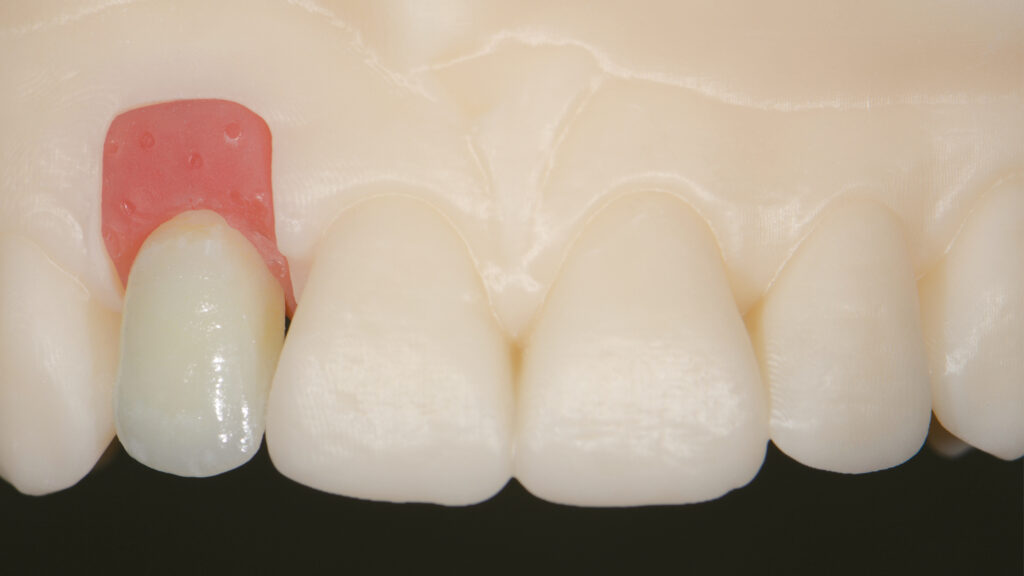

Herstellung des Eierschalen-Provisorium (TempShell)

Die STL-Datei der provisorischen Implantatkrone wird automatisch erzeugt, ein TempShell (Eierschalenprovisorium) konstruiert und die STL-Datei exportiert. TempShell ist ein verschraubtes Provisorium, das noch am Tag des chirurgischen Eingriffs eingesetzt werden kann. Es wird für jeden Patienten digital erstellt und kann mit DTX Studio Suite einfach an die Implantatposition angepasst werden. Anhand des Datensatzes wird CAD/CAM-gestützt das Provisorium aus PMMA gefräst (Abb. 11). Das gefräste Provisorium (TempShell) hat zwei Flügel. Diese sorgen für die richtige Position und Stabilität im Mund (Abb. 12 und 13). Durch On-Screen-Design-Verfahren passt das Provisorium perfekt auf das gedruckte Modell und in den vorgeschliffenen Gingivaverlauf (Abb. 14).